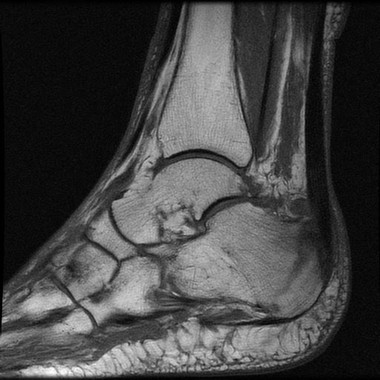

De esta manera, el cirujano conoce de forma más precisa cómo debe tratar cada fragmento del hueso roto en la planificación preoperatoria, evitando errores de cálculo o incertidumbres que suelen presentarse en intervenciones de gran complejidad. En un estudio, publicado en la revista Comput Methods Programs Biomed los expertos han confirmado el éxito de este método en casos de fractura por impacto en huesos de tobillo, que suelen ser las lesiones de mayor complicación por la cantidad de piezas afectadas.

El método identifica las heridas de una manera exacta partiendo de una imagen obtenida por tomografía axial computarizada (TAC), una prueba diagnóstica de rayos X que permite observar el interior del organismo en forma de cortes transversales o tridimensionales. Así, se puede conocer a priori y de forma precisa si se observan solo partes óseas o también hay músculos, tendones u otro tipo de tejidos blandos que no se diferencian en una radiografía convencional.

Con estas imágenes y la aplicación creada por los investigadores se muestra el número de piezas, la orientación y separación y se marcan las zonas de contacto entre ellas, incluso si la imagen aparece rotada, es decir, que alguna parte no sea visible desde la representación inicial. El sistema completo podría compararse con la marca por separado de cada parte de un puzle para conocer previamente cómo recomponer la totalidad. El algoritmo creado calcula la zona de unión entre dos fragmentos óseos que se separan y etiquetan desde las imágenes del TAC generándose una serie de puntos para cada trozo de hueso, lo que permite que las partes puedan alinearse de dos en dos.

El enfoque que se muestra en este artículo se aplicó con éxito en diferentes casos de traumas en el área del tobillo, una de las más complicadas en cirugía traumatológica. El sistema calculó de manera precisa en todos los casos clínicos probados que no existían solapamientos o espacios visibles entre los fragmentos.